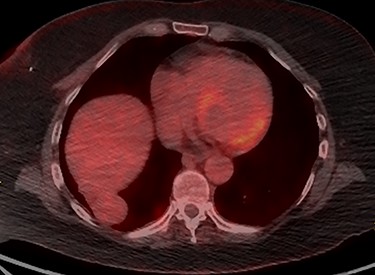

A 65-year-old female, with a background history of breast cancer, presented with dysphagia. Physical examination was unremarkable. Computed tomography (CT) scan of neck and thorax (Fig. 1) revealed a 4.2 cm supradiaphragmatic pleural-based mass. This had gradually enlarged over the preceding 2 years (original size 1.7 cm) and was reported as suspicious of pleural fibroma. Subsequent positron emission tomography (PET) scan (Fig. 2) revealed a smooth, mildly avid peripheral/pleural-based 4.2 cm right lower lobe lung mass with a maximum standardized uptake value (SUVmax) of 4.3, contiguous with the right hemidiaphragm. Multidisciplinary team meetings were held, and the experts concluded that there was a clear cleavage plane between the slow growing mass and liver. The mass was thought to represent a solitary fibrous pleural tumour, and hence the decision for resection was made.

PET scan of Thorax demonstrating a smooth mildly avid peripheral/pleural-based right lower lobe mass with SUVmax of 4.3, which was contiguous with the right hemidiaphragm.